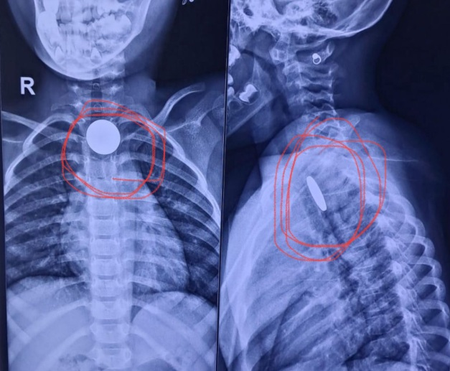

विभाग प्रमुख डॉ. योगेश गज्जर ने बताया कि पहले मामले में दो वर्षीय बच्चे को गले में तेज दर्द और उल्टी की शिकायत के साथ अस्पताल लाया गया था। जांच में पता चला कि बच्चे की आहार नली में सिक्का फंसा हुआ है। स्थिति गंभीर थी, क्योंकि सिक्का श्वसन नली के करीब अटक गया था, जिससे सांस रुकने का खतरा था। हालांकि डॉक्टरों की टीम ने ऑपरेशन कर बच्चे की आहार नली से सावधानीपूर्वक सिक्का निकाल लिया।

दूसरा मामला साढ़े चार साल के एक बच्चे का था, जिसने खेल-खेल में सिक्का निगल लिया था। कुछ ही देर बाद बच्ची को गले में दर्द और खाना निगलने में परेशानी होने लगी। परिजन उसे सिविल अस्पताल लाए, जहां ईएनटी विशेषज्ञों ने एक्स-रे द्वारा स्थिति की पुष्टि की। डॉक्टरों ने सावधानीपूर्वक बच्चे की आहार नली से सिक्का निकाला।